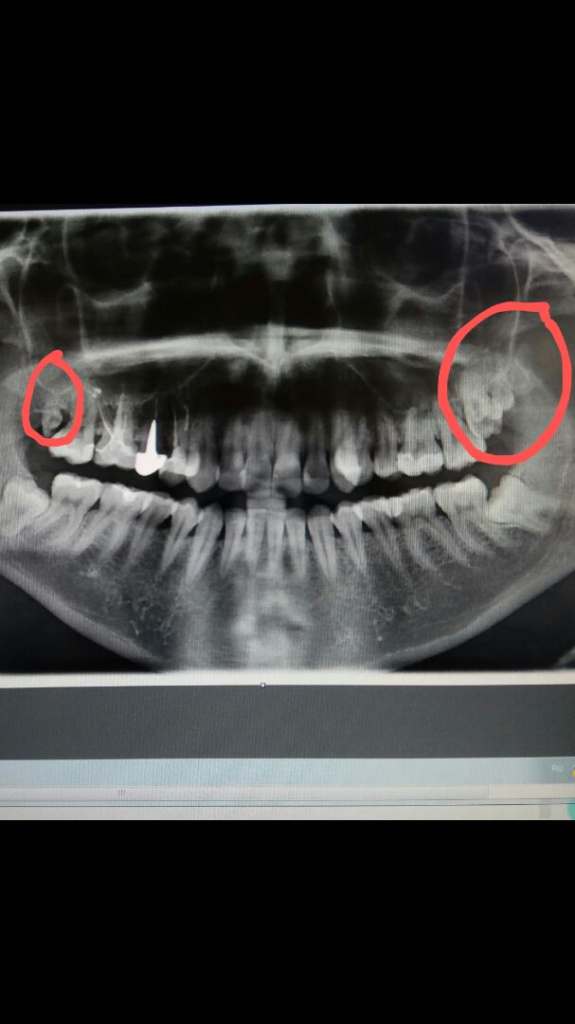

На приеме пациентка А. с жалобами на наличие 9-х зубов. После проведённой ортопантомографии выявлено наличие 1.9 и 2.9 зубов. Так как пациентка готовиться исправить прикус ( скученность зубов) предложено удаление 8-х и сверхкомплектных зубов. Плановая санация полости рта .

Если лишние единицы не прорезались, то из-за полиодонтии обычно не возникает неприятных ощущений. Поэтому нередко о существовании сверхкомплектных зубов мы узнаем лишь во время рентгенографии.

Выявить полиодонтию помогает рентгенодиагностика .

Обнаружить ретенированные сверхкомплектные зубы можно наверняка только с помощью рентгенологического обследования.

Конечно, многие врачи рекомендуют панорамную рентгенографию, но на 2D-снимке не всегда достаточно точно видно положение зачатков, так как зубы могут накладываться друг на друга.

Увидеть непрорезавшиеся лишние единицы и посмотреть на них со всех сторон можно благодаря 3D-снимку, сделанному с помощью компьютерной томографии. Так врач может составить полную клиническую картину и решить, стоит ли удалять сверхкомплектные зубы и как это сделать.